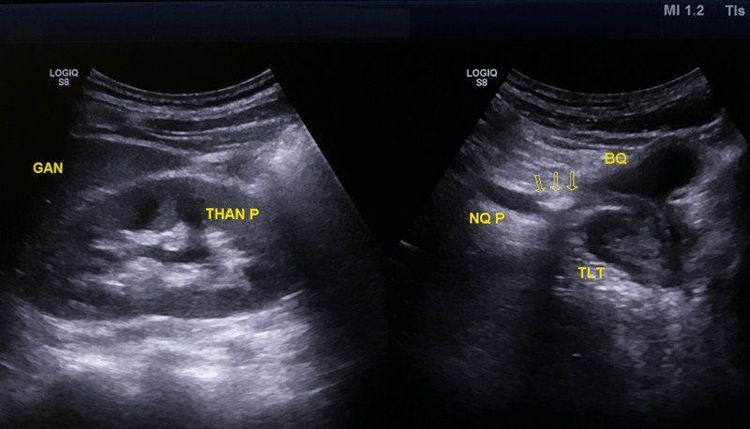

Siêu âm sỏi niệu quản là một trong những phương pháp hữu hiệu để chẩn đoán các bệnh lý hệ tiết niệu, đặc biệt là sỏi niệu quản. Kỹ thuật này có sử dụng các sóng siêu âm để cho hình ảnh chính xác, rõ nét về căn bệnh. Từ kết quả siêu âm các bác sĩ có thể đánh giá tình trạng, giai đoạn và sớm phát hiện các bệnh lý đường tiết niệu, trong đó có bệnh sỏi niệu quản.

Đây là một phương pháp chẩn đoán hình ảnh rất tốt để phát hiện bệnh sỏi niệu quản. Kết quả siêu âm sẽ cho biết số lượng, kích thước của sỏi và đánh giá mức độ ứ nước của thận và các biến chứng sớm quanh thận. Không dừng lại ở đó, phương pháp này còn rất dễ thực hiện tính an toàn cao, có lợi trong khám chữa bệnh cho trẻ em và những người thiếu hợp tác.

Chẩn đoán hình ảnh có vai trò quan trọng để xác định bệnh và giai đoạn bệnh sỏi niệu quản. Nhờ vào hình ảnh siêu âm, bác sĩ có thể:

• Biết được số lượng, kích thước của sỏi niệu quản và sỏi thận.

• Xác định vị trí sỏi niệu quản.

• Xác định độ dày mỏng và các tổn thương ở nhu mô thận.

• Xác định kích thước thận, niệu quản và đánh giá chức năng lưu thông của thận.

• Đánh giá được tình trạng giãn đài bể thận và tổn thương đài bể thận.

• Các biến chứng sớm quanh thận

Vai trò của siêu âm đánh giá, chẩn đoán bệnh sỏi niệu quản rất quan trọng, phương pháp này không chỉ giúp các bác sĩ đánh giá được các tổn thương, bệnh lý gặp phải tại hệ tiết niệu mà phương pháp này có thể kết hợp với chụp X - quang để cho kết quả chính xác hơn. Từ đó giúp bác sĩ đưa ra phương pháp điều trị phù hợp với từng người bệnh.